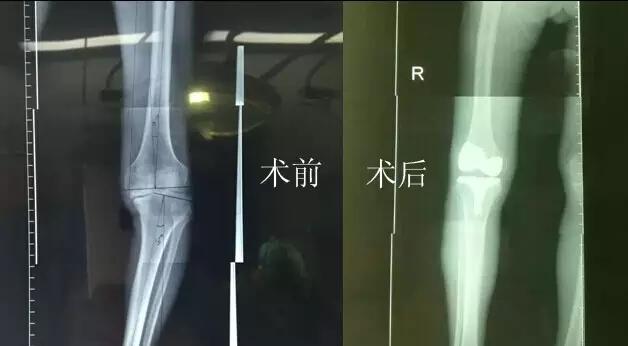

“嚴(yán)老伯的右膝患有重度關(guān)節(jié)骨性關(guān)節(jié)炎,右膝內(nèi)翻畸形,如果再晚點(diǎn)來(lái)就醫(yī),他的狀況還會(huì)持續(xù)變壞。”危立軍替嚴(yán)老伯仔細(xì)檢查之后說(shuō),“鑒于他的情況,我們建議實(shí)行人工膝關(guān)節(jié)表面置換術(shù)。”

2月26日,嚴(yán)老伯在廣安醫(yī)院關(guān)節(jié)科做了膝關(guān)節(jié)表面置換手術(shù),從切開(kāi)到縫合結(jié)束僅花了一個(gè)半小時(shí)。手術(shù)全過(guò)程病人基本上沒(méi)有手術(shù)后切口疼痛感,出血量不到150ml。術(shù)后第二天,他的右腿就能伸直了。

今天上午,主治醫(yī)生危立軍巡查病房時(shí)說(shuō):“嚴(yán)老伯的手術(shù)很成功,病人是非常嚴(yán)重的屈曲攣縮并內(nèi)翻畸形,膝關(guān)節(jié)平臺(tái)內(nèi)側(cè)骨缺損很嚴(yán)重。但我們采取了目前國(guó)際上最先進(jìn)的手術(shù)方法,無(wú)痛化病房管理和快速康復(fù)理念,所以病人恢復(fù)很快。”

據(jù)了解,以前像做這樣的手術(shù),病人大概需要休息兩個(gè)月左右才能逐漸康復(fù),而采取新的手術(shù)方法,按照嚴(yán)老伯目前恢復(fù)的情況,不需要什么特殊康復(fù),一周左右就能下地行走,兩周后就能出院。嚴(yán)老伯和家人對(duì)這次手術(shù)也表示非常滿意,他的關(guān)節(jié)內(nèi)翻也恢復(fù)到正常人一樣。